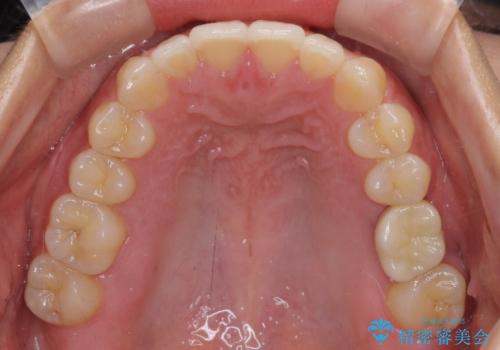

インプラントによる補綴治療とインビザライン矯正

- 抜歯が必要と診断された奥歯を気にして来院された患者様です。

抜歯の上インプラントによる補綴治療を行うこととなりましたが、前歯の叢生も気になるとのことで並行して矯正治療を行うこととしました。

歯列不正は軽微であったので、インビザラインによる矯正治療とし、矯正治療中にインプラント埋入を行う予定としました。

痛みがないので、ボロボロのまま放置していましたが、抜歯後は汚れが溜まりにくくなりスッキリとしたようです。

前歯のデコボコも解消され、ブラッシングが楽になりました。